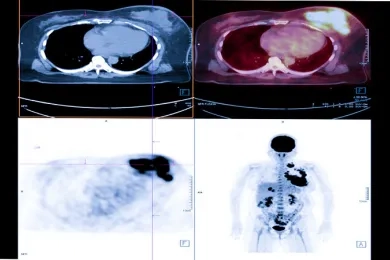

Nuclear Medicine methods are increasingly used in the treatment of cancer, as well as imaging. Targeted atomic therapies have been developing at a stunning pace since 2010.

Theragnostic is a field of medicine that combines patient-specific and disease-targeted diagnosis with treatment. The most important feature of atomic treatments with radionuclides is that the diagnosis can be made with the same drugs, and this provides an extraordinary advantage in cancer treatment. This feature ensures that the drug given for treatment, the area where it will reach in the body, and its effect on the diseased tissue are known precisely before the treatment. This approach is called the “theragnostic” approach.

Unlike conventional chemotherapeutics, theragnostic drugs go directly to the cancer cell, with little or no effect on normal cells. Thus, while healthy cells suffer the least damage, targeted therapy is performed by giving maximum damage to diseased cells such as cancer cells.